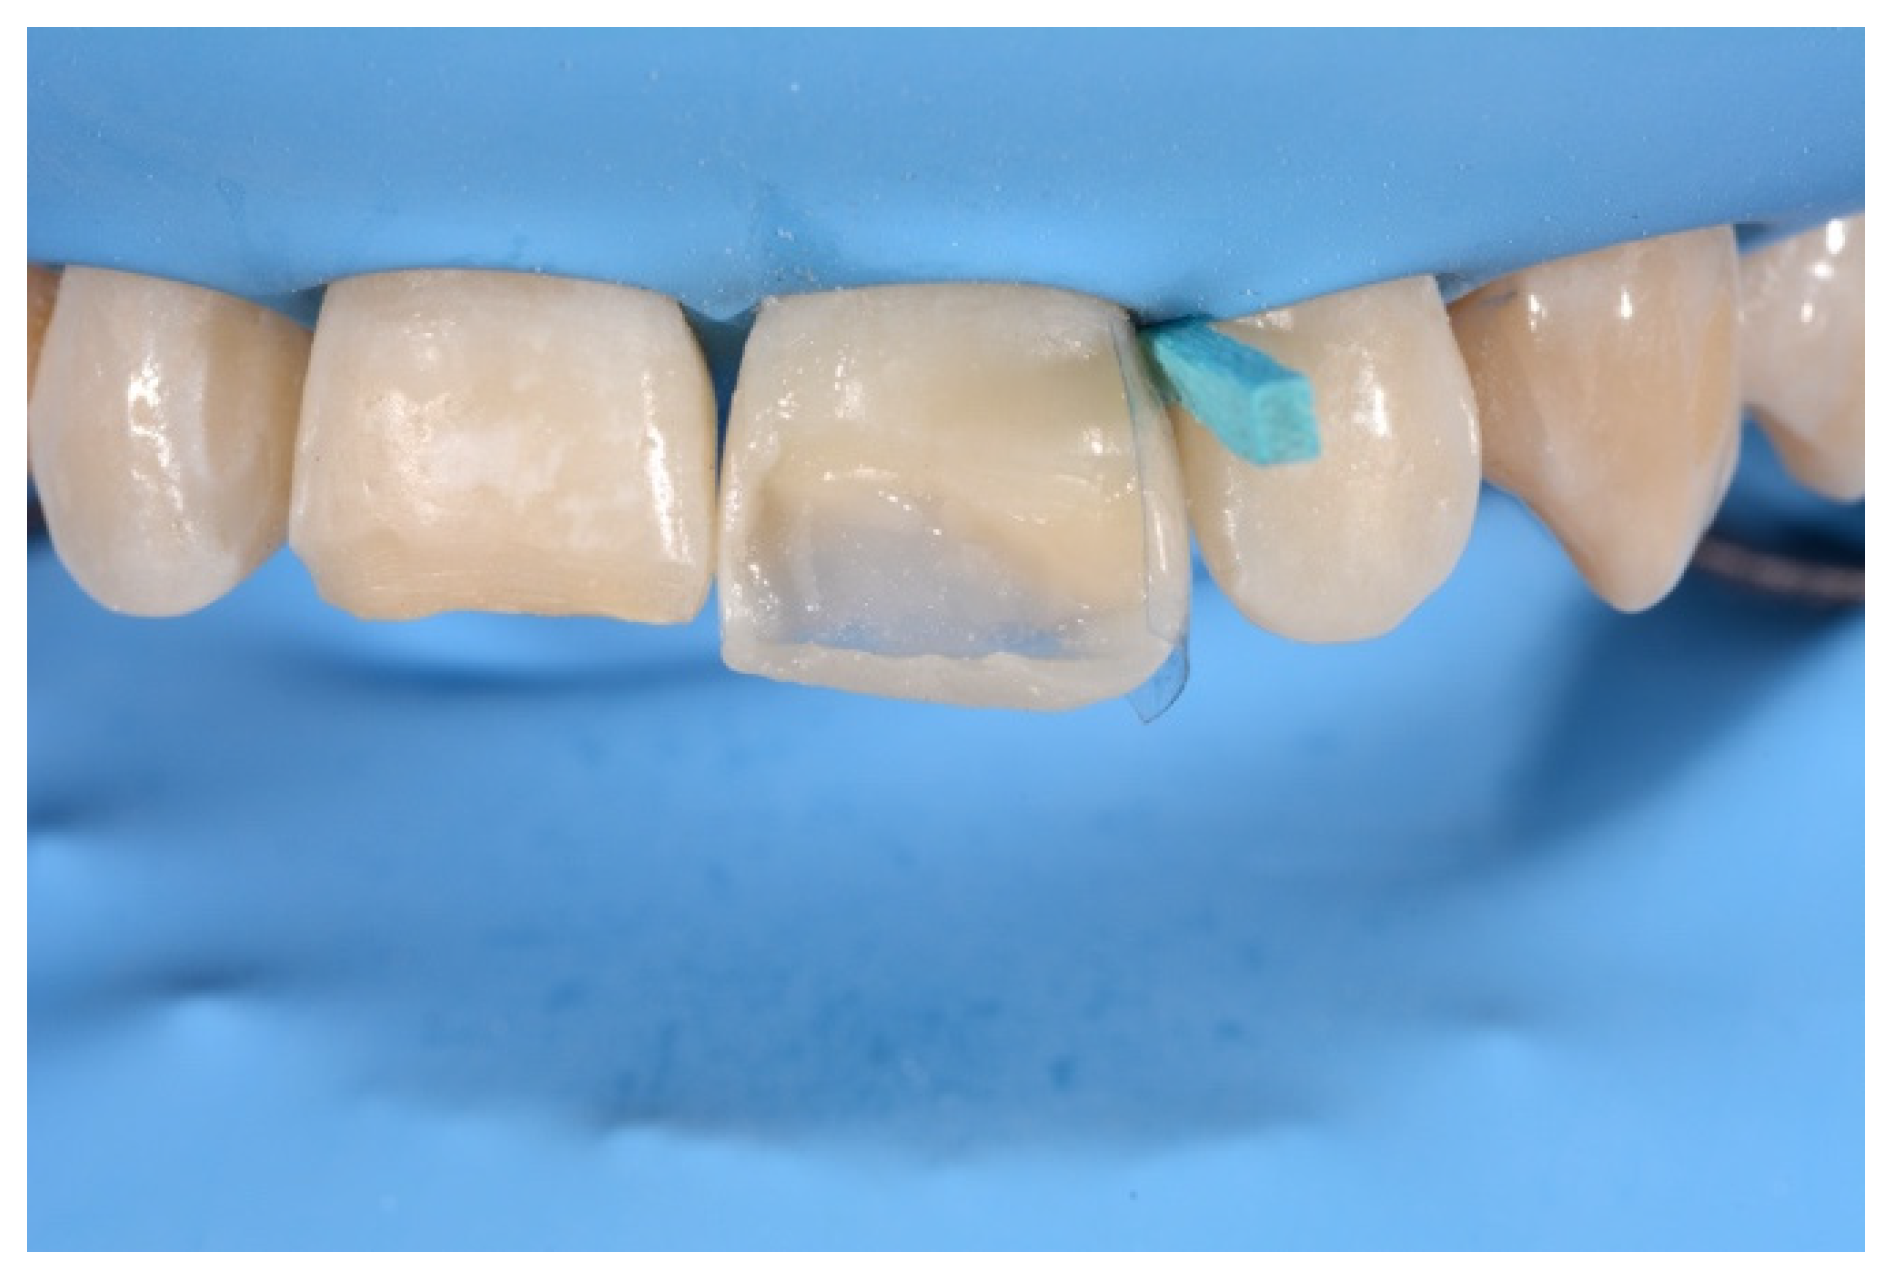

- Building interproximal walls with matrices;